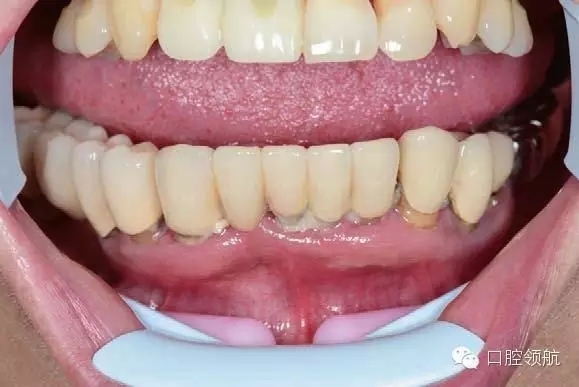

圖6-7 術前口內照片

下頜為十數年前制作的三組金屬烤瓷橋修復體。右下4、5、7帶缺失的6;右下3、1及左下1、2帶缺失的右下2;左下3、4、5、8帶缺失的6、7,左下8修復后牙齒自然脫落,全景片無左下8的影像。幾乎所有的余留牙周圍的骨質均吸收到根尖1/3。臨床上三組下頜金屬烤瓷橋均有較大幅度的松動(圖6-7,圖6-8)。